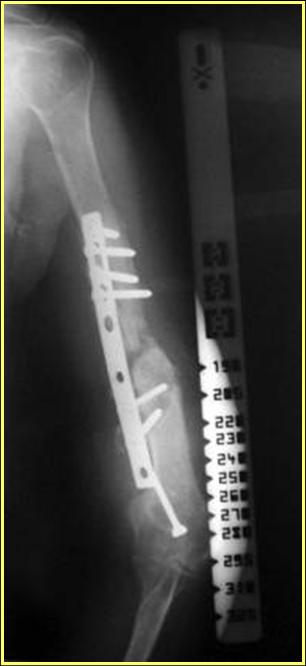

Типичная положительная ситуация для интрамедуллярного остеосинтеза с

использованием опорного металлокаркаса для компенсации дефекта.

Рентгеновская версия реконструкции. хронология:

после операции, 2 мес. после операции, через 1 год